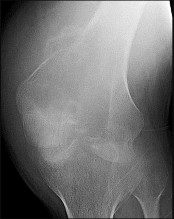

Figures 5a and 5b are the radiographs of a 74-year-old man with poorly differentiated squamous cell carcinoma of the lung. He has had an uneventful recovery after undergoing a wedge resection of his left upper lobe 6 months ago. He is experiencing left lateral knee pain, and a whole-body positron emission tomography/CT scan shows no avid area other than the lateral left distal femur. This patient has needed to use a wheelchair for 3 weeks because of his pain. You discuss these treatment options: aggressive curettage, local adjuvant treatment, cementation, and prophylactic fixation vs distal femoral resection and megaprosthesis total knee arthroplasty reconstruction. You should tell him that

Distal femoral megaprosthetic reconstruction after tumor resection is a reliable oncologic procedure, but 5-year implant survival is as low as 74% with an approximate 8% deep infection rate. The amputation rate is as high as 8% because of infection or recurrence, and there is an overall 18% revision rate. More than 10% of distal femoral megaprosthetic reconstructions are performed to address metastatic disease.

Fixation failure and infection may occur with either procedure. Radiation may not be recommended after a megaprosthesis reconstruction unless margins are not free of tumor. Either operation may be equally successful in returning patients to functional activities. Overall disease-free survival is related to the aggressiveness of the tumor and not the type of reconstruction performed.